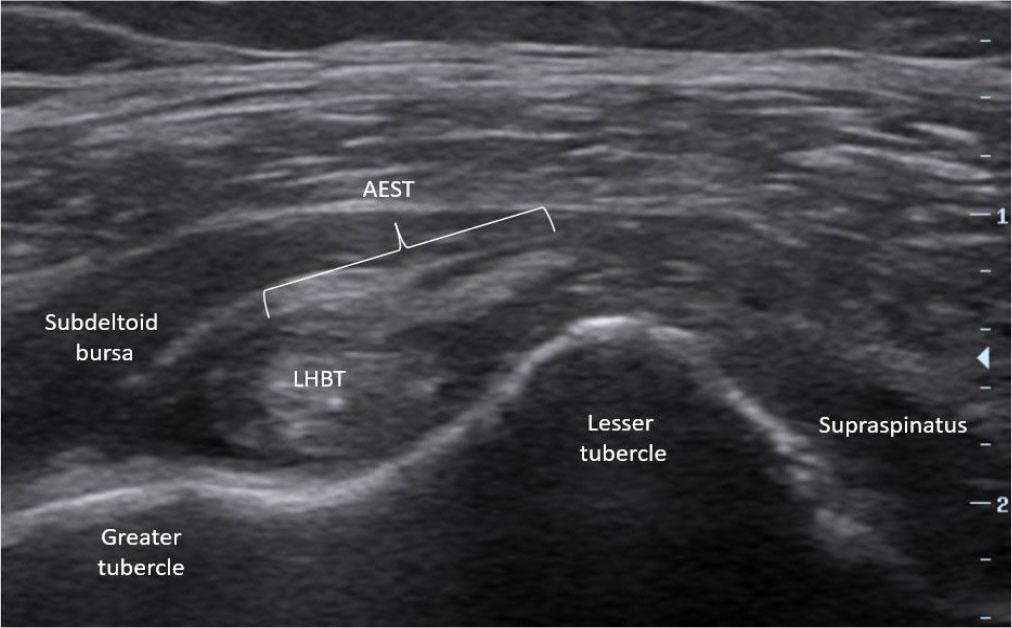

Mild intrasubstance tear of aponeurotic expansion of the supraspinatus tendon (AEST) at the base of the supraspinatus tendon in the right shoulder (AEST–supraspinatus classification: Ia, case 1)

The most frequent subtype was Ia (6/19, 31.6%), with mild intrasubstance AEST tears (Fig. 9), occasionally with ganglion formation (Fig. 10). Subtype IIIa (4/19, 21.1%) involved complete supraspinatus tendon tears with retraction. Subtype IIb (3/19, 15.8%) included one mixed IIb+Ia case with a lateral tear plus intrasubstance lesion.